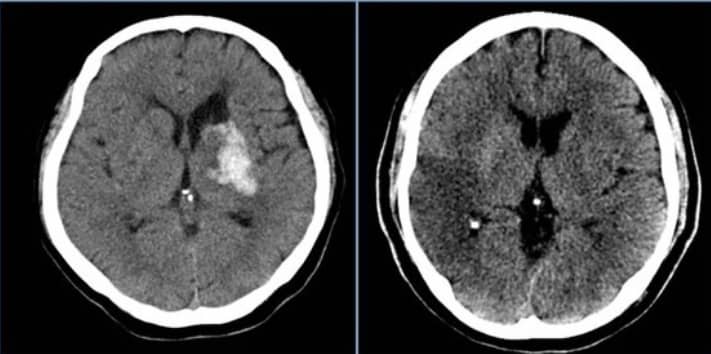

뇌 내에서의 출혈 여부를 파악하기 위해 컴퓨터 단층 촬영기(CT) 또는 자기공명영상진단(MRI)과 같은 고급 진단 기술이 사용됩니다. 특히, 지주막하에 출혈이 의심될 때에는 뇌혈관의 조영 검사를 통해 문제가 되는 동맥류를 정밀하게 파악하게 됩니다.